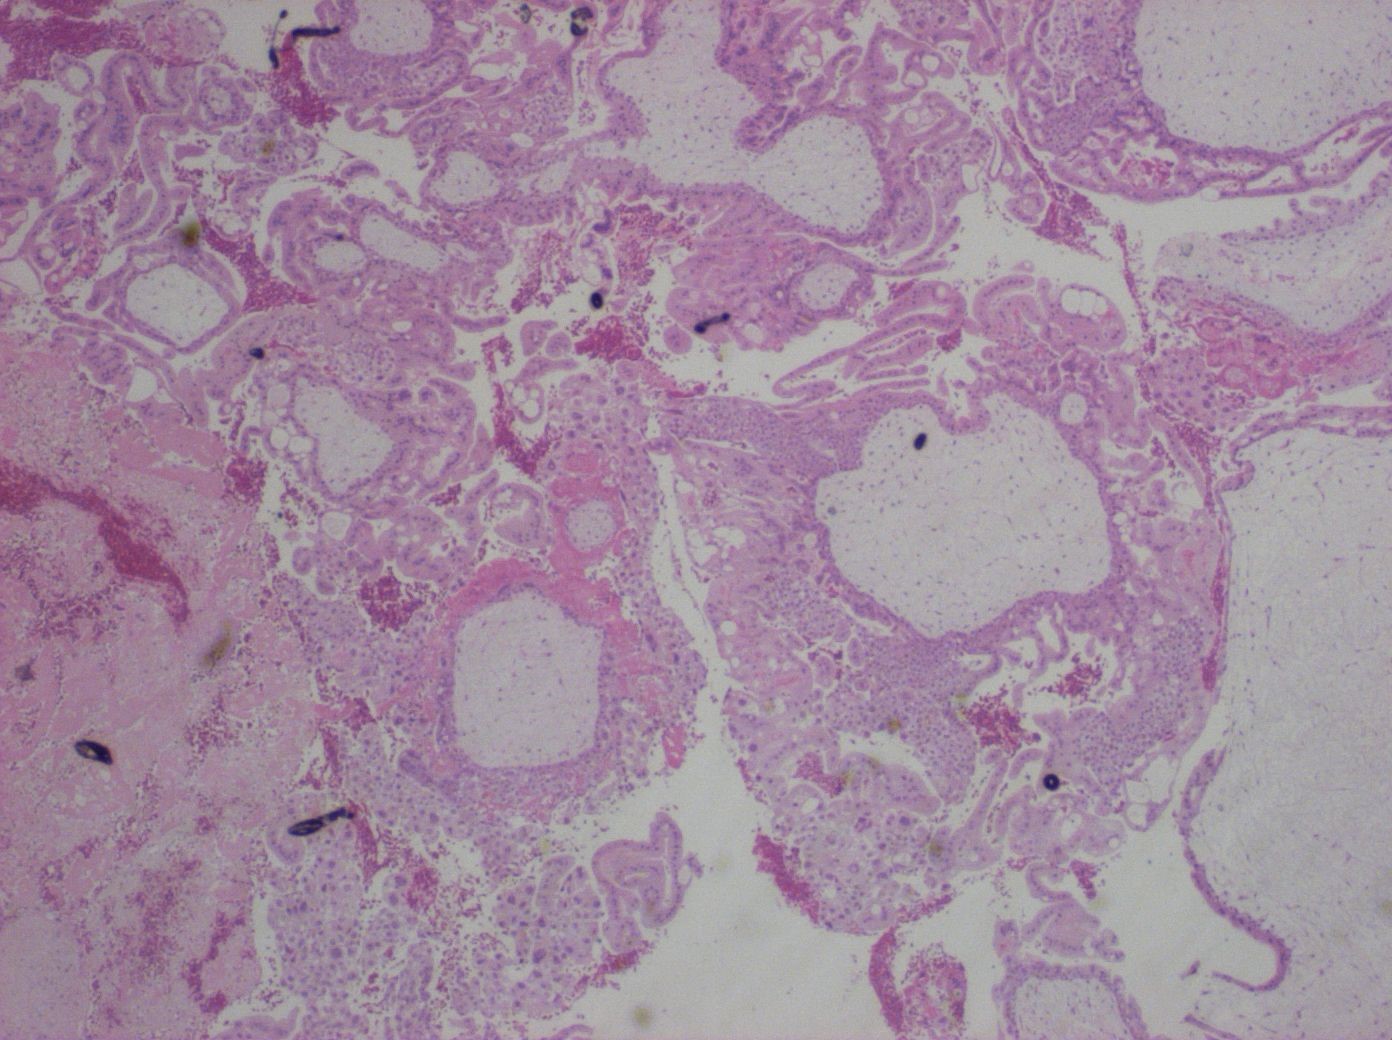

Komplett mola hydatidosa

Kompletta molor är genetiskt diploida med allt kärn-DNA av paternellt ursprung (undantag ärftliga molor enl. ovan).

Mikroskopiskt ses i typiska fall en väl utvecklad hydatiform omvandling av alla villi med ödem och cisternbildning samt circumferent trofoblasthyperplasi med cytologisk atypi 136. Tidig komplett mola kan ha mindre uttalade förändringar. Foster och amnionhinna förekommer inte, men vaskulära korionvilli kan återfinnas i tidiga fall. Dessa kärlstrukturer är dock vanligen tomma 137.